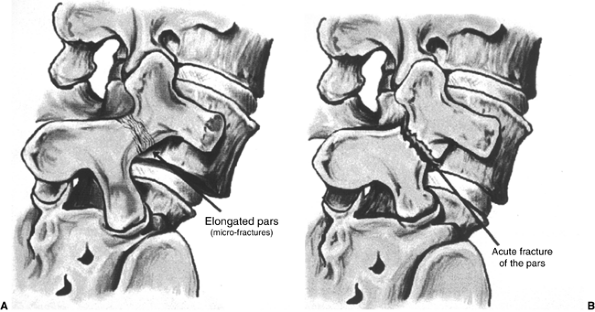

![]() |

Figure 21.6 Sketches of an elongated pars interarticularis (A) and an acute fracture of the pars interarticularis (B) across the neck of the “Scotty dog.”

|